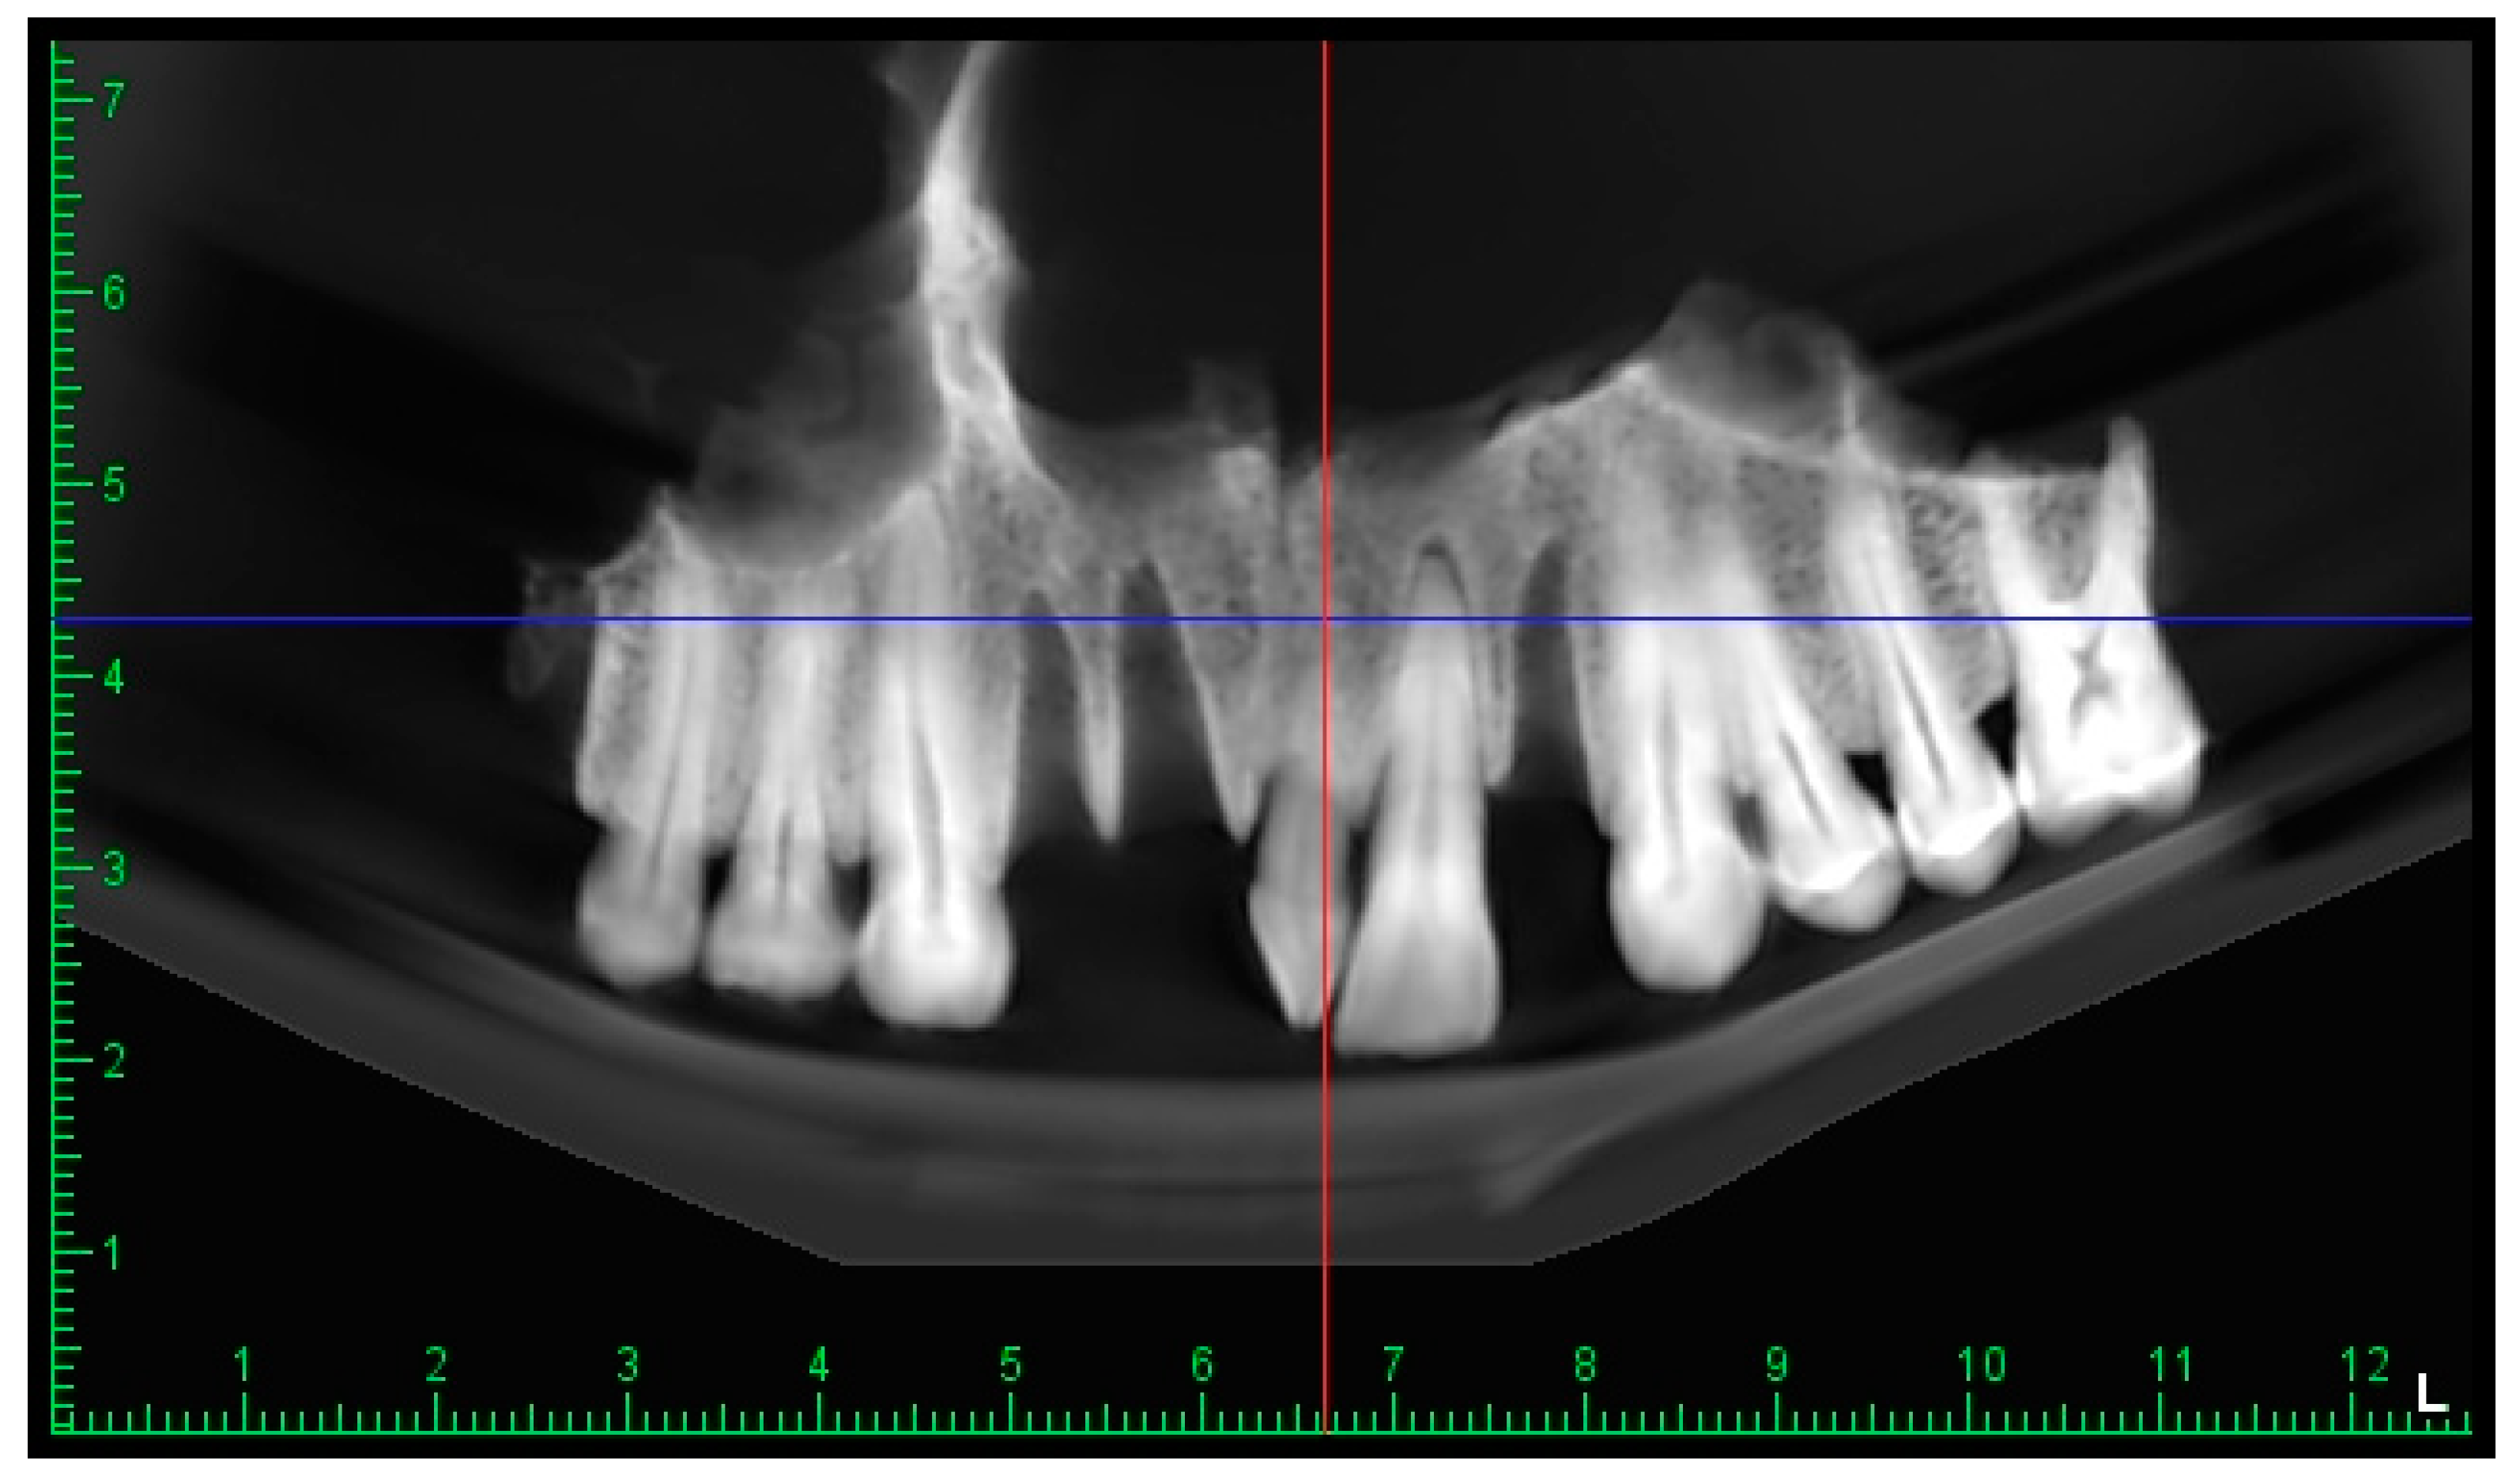

3.3. The CBCT Scan

3.2.5. The Mesiodens

3.2.3. The Teeth